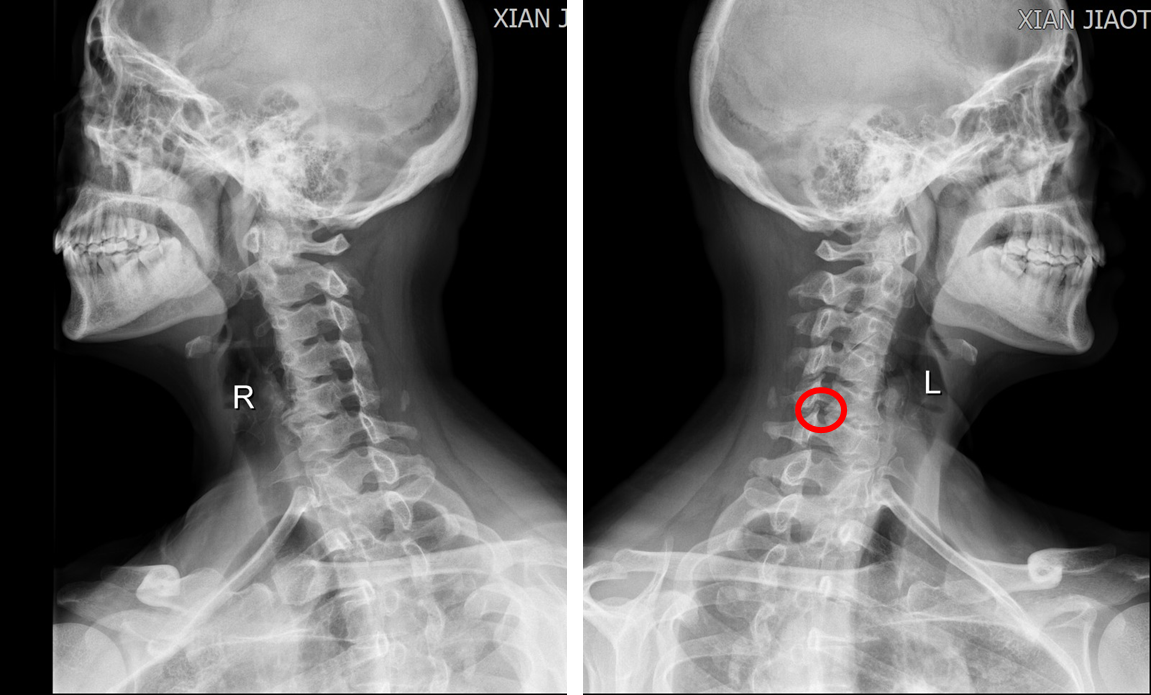

图2颈椎双斜位片(左侧颈5/6钩椎关节增生明显)

来自陕西省渭南市的许某被头晕症状折磨了8年之久,犯病时伴有濒死感、心慌、胸闷、气短、大汗,偶尔伴有耳鸣及听力减退等症状,十分痛苦。反复就诊于不同级别的医院,要么被误诊为颅内疾病、冠心病、或高血压等疾病,结果治疗无效;要么确诊为颈椎病,但因未接受手术治疗,导致症状反复无法缓解。1月前患者怀着忐忑的心情就诊于我院神经内科,展淑琴主任团队快速给患者完善了颅脑MR 3T平扫、头颅MR血管成像、颈部MR增强血管扫描等专科检查,均未见明显异常(图1),考虑该患者头晕可能与颅内疾病关系不大,于是联系耳鼻喉科、骨科中心骨病与创伤病区等多学科会诊。张纯主任通过详细询问病史、认真查体后初步考虑该患者头晕可能系颈椎病所致,并嘱患者完善颈椎MRI及颈椎正侧双斜位片检查进一步确认。经过仔细查阅加拍的影像学检查,张纯主任发现,患者颈4/5、颈5/6椎间盘突出严重,相应椎管狭窄;最为重要的是颈椎双斜位片上左侧颈5/6钩椎关节增生明显(图2),且从MRI轴位片上可以看到椎动脉在颈5/6层面存在受压(图3),于是向患者告知病情,并果断建议其手术治疗。患者饱受头晕困扰,鉴于张纯主任每次交流中均展现出的专业素养和工作态度,患者毫不犹豫地选择手术治疗,遂转入骨科中心骨病与创伤病区。经过骨三科护理团队专业的术前准备和医生团队详细的术前规划,在麻醉团队、手术护理团队的保驾护航下,张纯主任主刀,高宗强主任医师及李永伟博士协助,为患者实施了颈椎前路椎管减压术,术中张纯主任仔细操作,反复检查椎动脉减压效果,直至减压满意。术后3天给与患者复查术后X线片,显示非常满意(图4)。患者下地活动后发现头晕症状完全缓解,出院后1周还特地与张纯主任取得联系,告知“现在一点都不晕了”。医生的专业判断、果断决策及精准手术,加之患者的高度配合,使得手术得以顺利、成功进行。